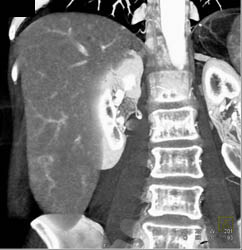

Huge Collaterals With Recanalized Umbilical Vein